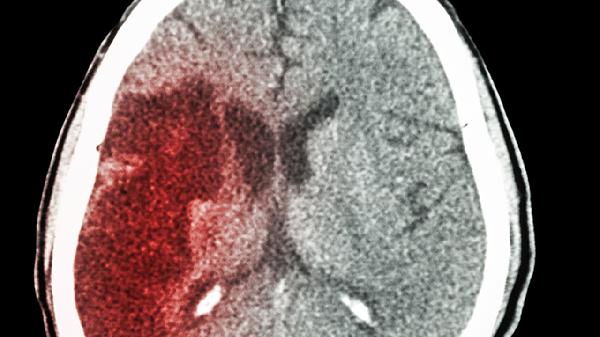

健脑益气片中的人参皂苷可扩张脑血管,增加脑组织氧利用率。适用于长期用脑过度导致的注意力不集中、思维迟钝等问题,能缓解因颈椎病或动脉硬化引发的脑供血不足性头晕。临床常配合血塞通片、银杏叶片等药物联合使用,但脑出血急性期患者禁用。